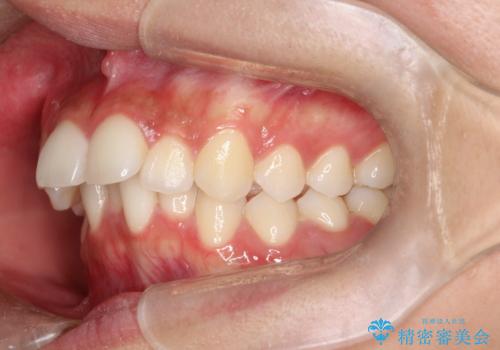

1. 【審美ワイヤー】口元を下げたいの治療前

2. 【審美ワイヤー】口元を下げたいの治療中